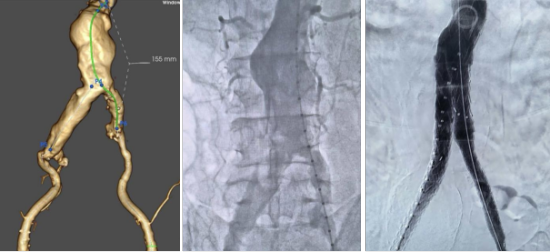

手术当日,佟志国医生团队展现了精湛的腔内手术操作技艺。在麻醉医师的密切配合下,凭借丰富的临床经验与精准的影像引导,将覆膜支架精准送达腹主动脉瘤病变部位。正当手术进入关键的支架释放阶段,患者突发过敏性血压骤降,麻醉团队即刻启动升压治疗与呼吸道管理,而佟志国医生团队临危不乱,始终保持操作的稳定性与精准性,顺利完成支架定位、释放与隔绝,成功封堵腹主动脉瘤,整个核心手术过程一气呵成,尽显松北院区血管外科在复杂腔内手术中的技术驾驭能力。

佟志国副主任介绍:腹主动脉瘤(AAA)并非肿瘤,而是腹主动脉因动脉粥样硬化、遗传、吸烟等因素,管壁结构受损变薄弱,在血流冲击下局限性扩张,如同血管壁上鼓起的“气球”。它被称为“不定时炸弹”,因瘤体多持续增大,直径超5cm破裂率达20%,超6cm升至40%,吸烟会加速扩张,且破裂后病死率高达90%,风险难以精准预判。早期多无症状,部分患者可摸到腹部搏动性肿块,后期可能出现腹痛等压迫症状。高危人群(65岁以上吸烟史者、75岁以上无吸烟史者、有家族史者等)需定期超声筛查。该病无法自愈,无根治药物,确诊后需戒烟、严控血压,小瘤体遵医嘱随访,达到手术指征可选择传统开放手术或微创腔内修复术,早发现早干预是降低风险的关键。